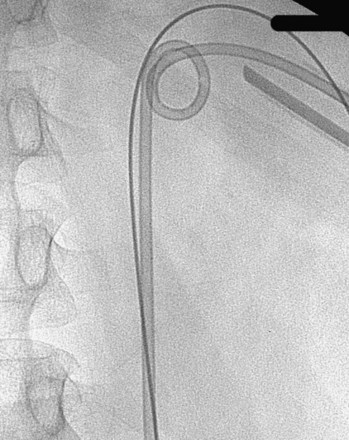

The “ultimate” retrograde assistance to percutaneous access into the upper urinary tract collecting system is the retrograde approach to percutaneous access. Although the antegrade approach is much more commonly performed, a retrograde approach may be selected when the surgeon has limited experience with antegrade percutaneous renal puncture or in situations in which there might be a technical advantage to the retrograde approach such as morbid obesity or a hypermobile or abnormally situated kidney (Mokulis and Peretsman, 1997). The Lawson Retrograde Nephrostomy Wire Puncture Set (Cook Urological; Spencer, IN) is the device commercially available for this use. After retrograde placement of a guidewire into the renal pelvis, pass the 7-Fr Torcon catheter—which is actively deflectable from 0 to 140 degrees (Fig. 47–14A)—over the guidewire and into the desired calyx. Insert the 3-Fr polytetrafluoroethylene (PTFE) sheath containing the 0.017-inch stainless steel puncture wire through the Torcon catheter. Advance the puncture wire through the kidney and body wall under fluoroscopic control, withdrawing and repositioning it if any obstacles such as a rib are encountered (Fig. 47–14B). Make a small skin incision and grasp the wire externally. Use the fascial dilators in an antegrade fashion until the Torcon catheter can be advanced through the tract. Once the end of the catheter exits the skin, exchange the puncture wire for a standard 0.035 inch guidewire, thus attaining through-and-through access.